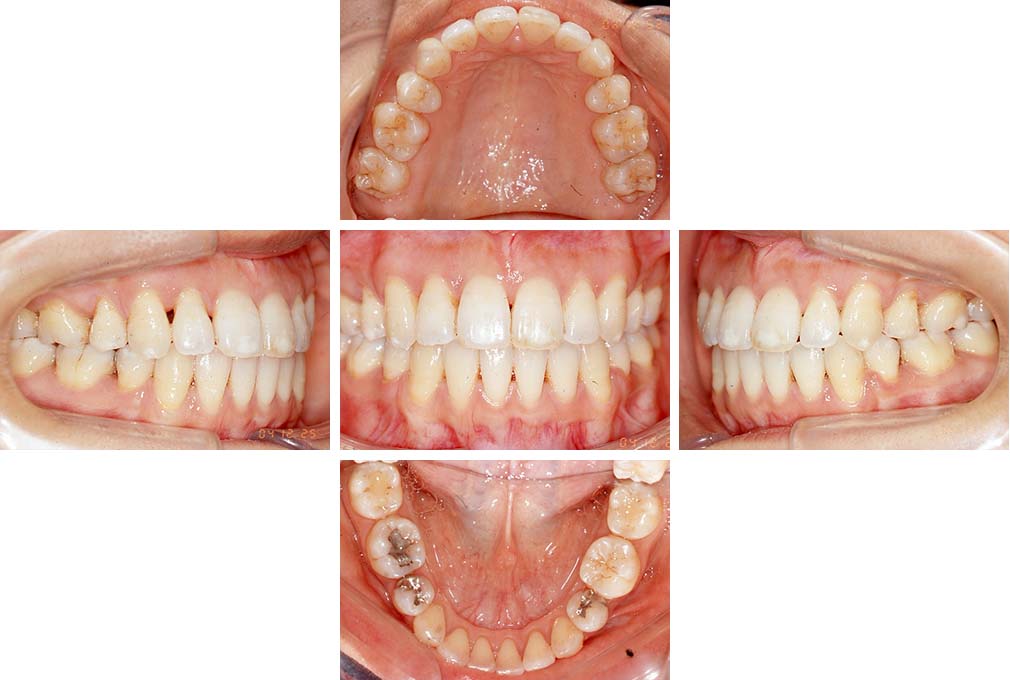

CASE:03

上下顎前突

初診時年齢 18歳4か月

性別 男性

治療費の目安 105万円程度(治療開始時)

歯列の乱れは著しくなく上顎右側側切歯が捻転し口蓋側へ転位していた。また、問診の中で患者さんから最も重視する治療結果として口元の突出の改善の申出があった。下顎が後退した上顎前突傾向ではあったが著しいものではなかった。上下顎前突と診断し上下顎小臼歯抜歯を行っていただき、上下顎舌側マルチブラケット装置を使用して、矯正用アンカースクリューを併用して動的治療を行った。上下顎前歯の後退を十分行い口元の突出感も改善した。治療後10年1か月の来院時には口元の突出感が再発することもなく、下顎前歯の少しの唇舌的なずれはあったが歯列は安定していた。動的治療期間2年2ヵ月間。

治療前

18歳4ヵ月

治療後

動的治療期間2年2カ月間

20歳10か月

10年経過

動的治療終了後10年1カ月

30歳11か月